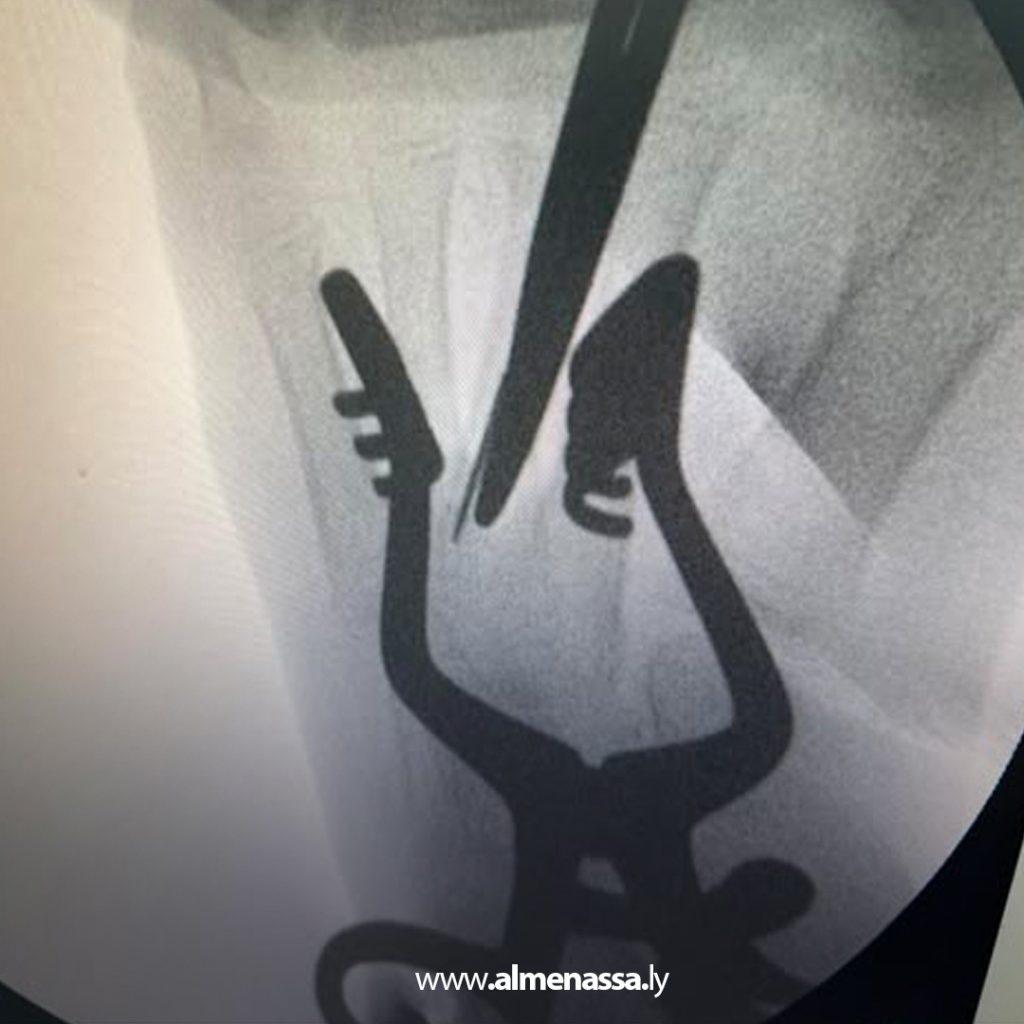

وتحدث استشاري جراحة العظام عن حالة تمكنت فيها الإبرة من ثقب العظم والدخول في العظم وبالتحديد داخل نخاع عظم مشط القدم مما يجعل هناك صعوبة كبيرة في استخراجها مبينا أنه كانت هناك محاولة لم يكتب لها النجاح لاستخراج هذه الابرة في المستشفى لصعوبة الوصول إليها.

ولفت لنقي إلى أن هذه العملية تتطلب فتح نافذة صغيرة داخل عظم المشط الثالث للقدم باستعمال صورة الأشعة السينية أثناء العملية لتحديد مكان الإبرة بشكل دقيق ومن ثم استخراج إبرة الخياطة المكسورة من داخل تجويف العظم لهذه المريضة ذات 5 سنوات.